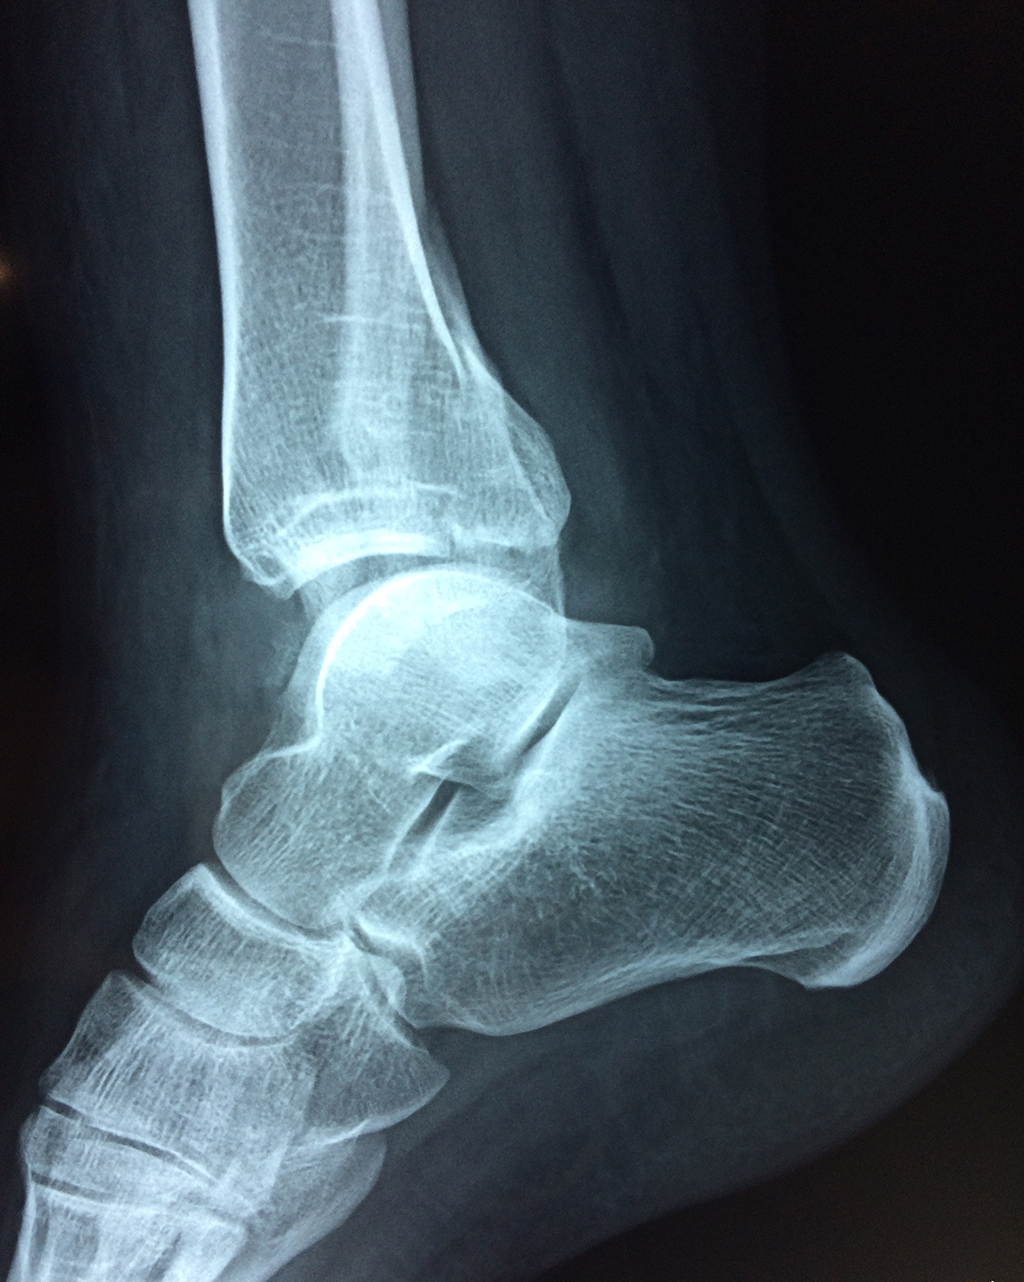

Una fractura de tobillo es la rotura de uno o más de los huesos del tobillo. Estas fracturas pueden ser:

Algunas fracturas de tobillo pueden requerir cirugía si:

- Los extremos de los huesos están desalineados entre sí (desplazados).

- La fractura se extiende hasta la articulación del tobillo (fractura intra-articular).

Cuando se necesita cirugía, es probable que esta implique el uso de clavijas de metal, tornillos o placas para sostener los huesos en su lugar mientras la fractura se consolida. Los elementos de soporte pueden ser temporales o permanentes.